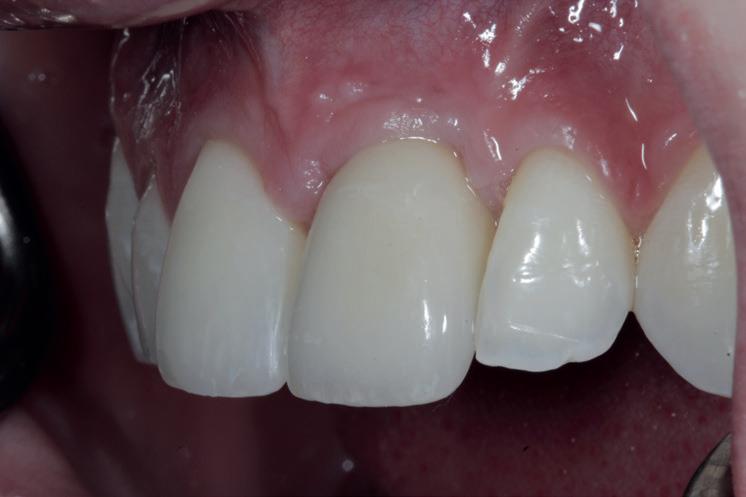

SITE AUGMENTATION Reconstituirea țesutului moale periimplantar și papilar în zona estetică

RECONSTITUIREA țesuturilor moi periimplantare. Scopul acestui raport de caz este de a demonstra procedurile chirurgicale utilizate pentru corectarea unui defect al țesuturilor moi periimplantare folosind țesutul moale interdentar în combinație cu tuberozitatea ca locație donatoare de țesut conjunctiv, utilizând o abordare prin tunelizare într-o zonă estetică.